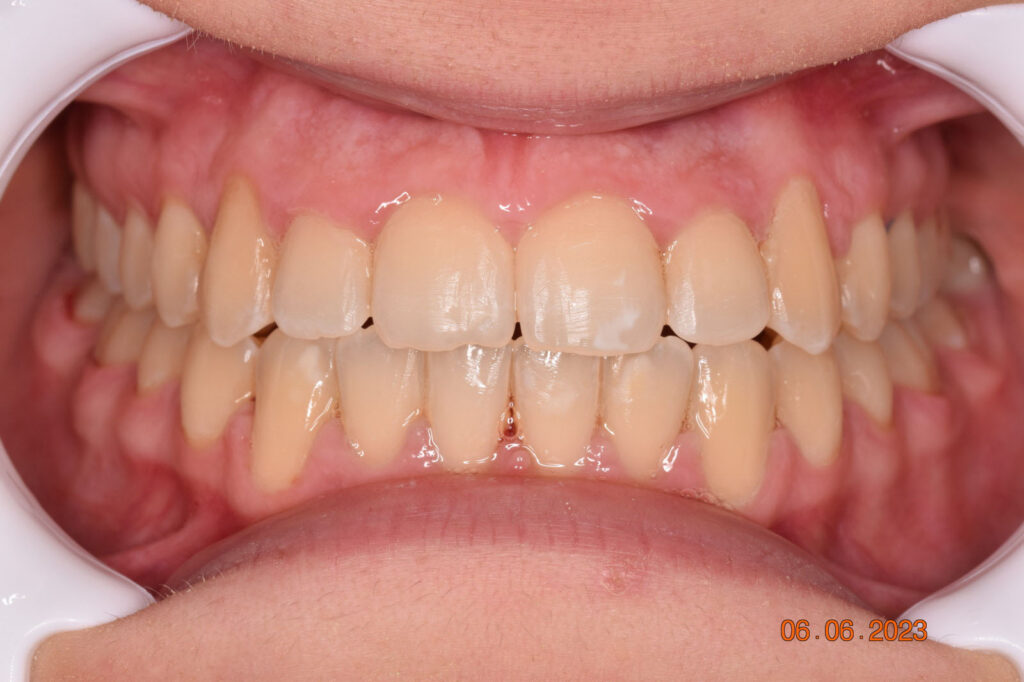

A 27-year-old female patient presented with class III malocclusion, 15 mm crowding in the upper arch, an anterior open bite, a lateral crossbite, and a total ABO score of 29. Her facial profile was straight with a retrusive maxilla, and the upper and lower incisors were retroclined. An extreme lack of midface support was also noted, and the constricted dental arches resulted in a poor smile width and dark buccal corridors. No myofunctional investigations were performed at the time, as they were initially considered unnecessary.

Adhering to the principles of Face First Orthodontics, the primary objective was to increase midface support by expanding the upper maxilla, fixing the cross bite, and aligning the teeth. Closing the open bite was a secondary objective.

The teeth are in a very good position and the bone has reshaped.